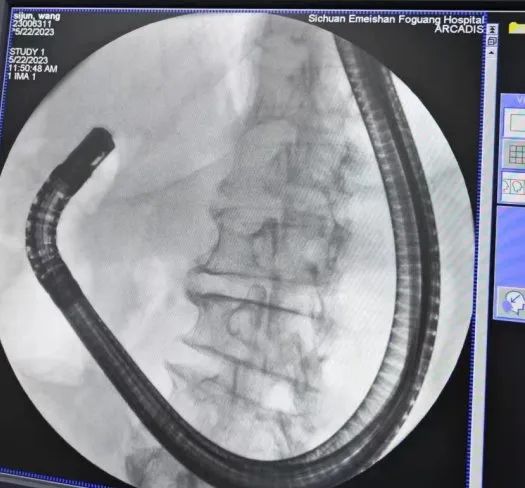

患者3年前因胃癌行胃大部切除术(毕II式),近期因“上腹部疼痛”收入肝胆胰外科治疗,经过完善腹部增强CT、MRCP、肝功等检查发现患有胆总管结石并梗阻性黄疸、肝功能不全,住院期间,患者出现发热,明确诊断胆总管结石伴急性胆管炎。需手术治疗。肝胆胰外科胡红强主任带领科室团队结合患者实际情况,制定了详细的多套手术方案,经与患者及家属充分沟通,最终选定行胃大部毕II式切除术后行ERCP取石。

肝胆胰外科主任胡红强介绍:“毕II式胃肠吻合术后行ERCP操作,上消化道途径较正常人体明显改变,需经更长肠内途径,十二指肠乳头逆行插管更困难,手术难度相对较高”。为了给患者制定科学、合适的治疗方案,经过科室详细地讨论并做好手术方案及备选方案后,最终决定首选全麻下ERCP(全麻下患者耐受性更好,为患者减轻不适反应)。

手术当天,胡主任带领整个团队顺利完成无痛ERCP取除胆总管结石,术后经鼻胆管造影未见残余结石。(供稿:峨眉山佛光医院)